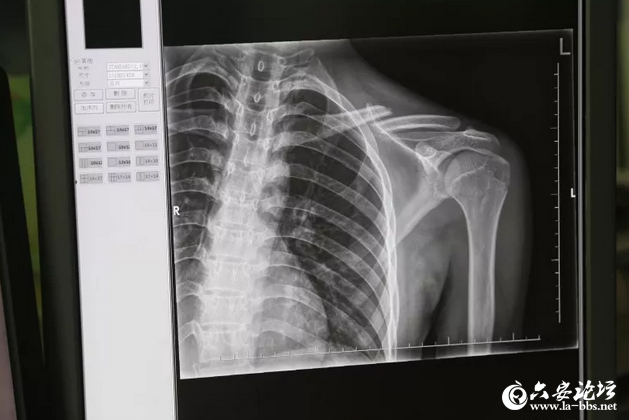

▲嫌疑人骨折拍片 随后,办案民警对周边城市也进行核查,发现2018年3月17日至4月7日间,在寿县某医院、凤台县某医院、长丰县某医院以及在肥西县某医院均有名为“丁某某”锁骨骨折的X光片子,这些X光片的记录,佐证了办案民警的推断,后经过调取医院监控录像,发现“丁某某”均为同一人。经过询问医生得知“丁某某”均无治疗情况,进一步证明了办案民警的推断。 长丰县公安局随即立案侦办,专案组经过缜密侦查,发现一个以曾某某、何某某等人为首,利用嫌疑人骨折旧伤,在全国境内实施诈骗的犯罪团伙。2018年5月17日,专案组通过线索研判得知,该团伙又有人在安徽安庆一带实施诈骗活动,专案组立即赶往安庆,在太湖县高速路口发现嫌疑人何某某和新招募的徐某,二人正乘坐一辆三轮车驶向太湖县人民医院。办案民警跟踪二人后发现,他们正以同样的手段诈骗这名骑三轮车的老人。办案民警当场出击,将拿到赔偿款准备离开现场的何某某、徐某抓获。经审讯得知,该团伙成员欧阳某某等人正在江西庐山后,专案组马不停蹄,连夜赶往庐山,将嫌疑人欧阳某某抓获。 辗转全国追捕流窜作案团伙经进一步侦查,办案民警发现曾某某为该团伙骨干成员,该男子有两次诈骗前科,其中2017年因诈骗,开车撞伤抓捕民警被江西省公安机关网上追逃。专案组民警综合情报线索后发现,曾某某正在广东一带活动。2018年5月30日,专案组民警在广东省清远市将犯罪嫌疑人曾某某抓获。 经审讯,该诈骗团伙先后在湖北,江西、四川、广东等地实施碰瓷诈骗。他们分工明确,主要是由曾某某在东莞等地招募20岁以下年轻男性,承诺给予10%的利润后,设法把他们的锁骨弄骨折,凭着“伤情”他们疯狂流窜作案。同时,曾某某还负责“伤者”的培训,让他们学习碰瓷的技巧。然后流窜到各地,由曾某某物色受害人伺机作案。何某某主要是陪伴受伤嫌疑人进行碰瓷,并带受伤嫌疑人去医院拍片子,在确认“骨折”后,何某某再以受伤嫌疑人朋友的身份打电话给曾某某,曾某某则以受伤嫌疑人家属的身份,在电话里和受害人讨价还价,每次诈骗一万元左右。作案地点均选择在市郊或县城附近监控较少地区,作案对象一般是三轮车或农用车的驾驶员。 目前,曾某某、何某某等人已被依法采取刑事强制措施,案件正在进一步办理中。